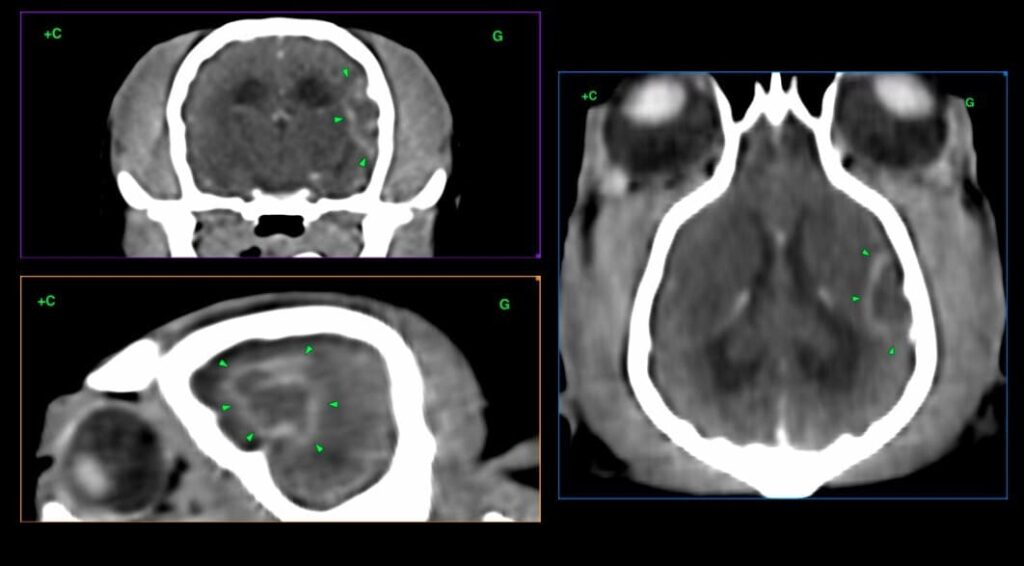

Cas clinique 1 – Scanner de « Isis » – lésion ischémique subaiguë dans le territoire de l’artère cérébrale moyenne